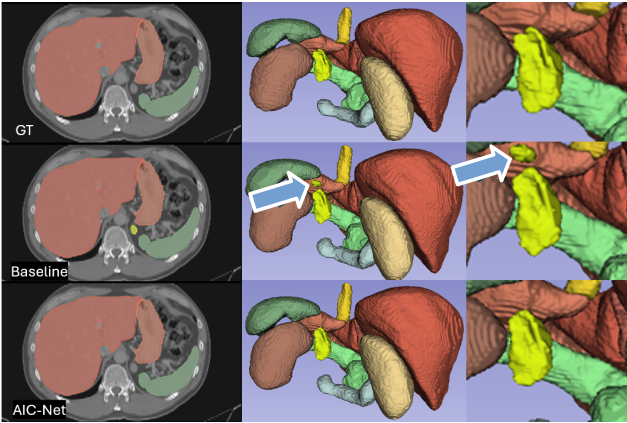

Figure 7: Qualitative comparisons on organ segmentation. The baseline method is suboptimal, resulting in the segmentation of additional spleen tissue, as indicated by the orange arrows.

The learned common prior, as well as accurate deformation, in our AIC-Net can promote anatomically accurate segmentation. This is supported by results in Figures 6, 7 and 8. In Figure 6, despite being over-smoothed, the deformed prior at the global level still provides accurate guidance for identifying vertebra indices, which in turn supports precise segmentation at the local level. In contrast, the baseline method appears to struggle with correctly identifying vertebra indices, leading to inconsistent predictions. We also observe that this mixing effect is a common issue in bone segmentation tasks (Wasserthal et al. 2023). In Figures 7 and 8, baseline methods give incorrect segmentation that result in separated spleen and left adrenal gland, which clearly violate human anatomy. For both cases, AIC-Net gives correct predictions.